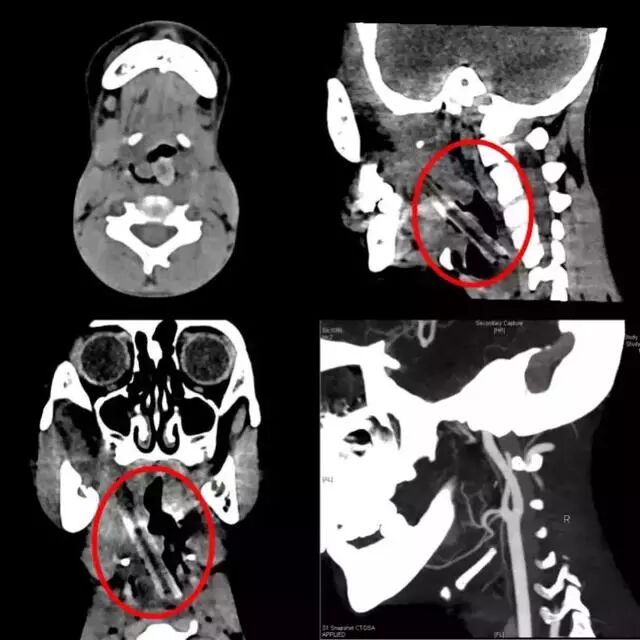

单从外表看,很难联想到内藏巨大异物。CT检查结果一出来,所有医生不禁倒吸一口气:“很少见到这样的情形!”

CT检查图片可见树枝位置

原来,检查结果显示,长达5厘米的树枝从小李右侧咽旁延续至左侧梨状窝,这个粗大的树枝随时影响到旁边狭窄气道的通气与进食。